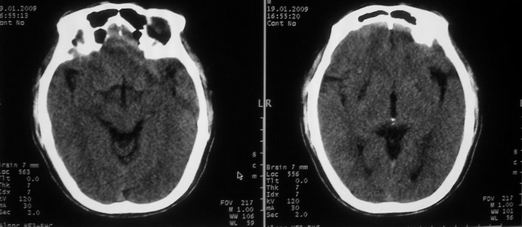

以下是引用随光逐影在2009-1-20 19:38:00的发言:[br]双侧豆状核对称性脑软化灶(中毒性脑病后遗改变?肝豆状核变性?)。

以下是引用jiangjing在2009-1-21 9:38:00的发言:[br]双侧豆状核对称性脑软化灶(中毒性脑病后遗改变?肝豆状核变性?)。